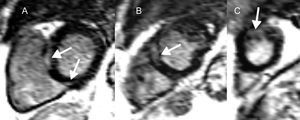

La sarcoidosis es una enfermedad granulomatosa y multisistémica que en el 2-5% de los casos afecta al corazon75,76. La inflamación miocárdica evoluciona a granulomas no caseosos y, a la larga, a zonas de fibrosis focal. Aunque la reentrada subyace a la AV relacionada con la cicatriz en las últimas fases, se han documentado actividad provocada y automaticidad anómala77. Se cree que el RTG refleja la actividad inflamatoria y la fibrosis y, en consecuencia, la fase aguda no puede diferenciarse de la fase crónica de la enfermedad (figura 4)78. Son múltiples los estudios (tabla 4)79-84 que proporcionan indicios de las implicaciones del RTG en la AV y la MSC.

Resonancia magnética cardiaca en la sarcoidosis cardiaca y riesgo de arritmias ventriculares y muerte súbita cardiaca. Cortes del ventrículo izquierdo de eje corto (A-C) que muestran realce tardío de gadolinio en la pared media y el epicardio (flechas) a nivel basal (A), medioventricular (B) y apical (C) en un paciente con sarcoidosis cardiaca. En esta enfermedad, tanto la presencia como la extensión del realce tardío de gadolinio se relacionan con arritmias ventriculares y muerte súbita cardiaca.